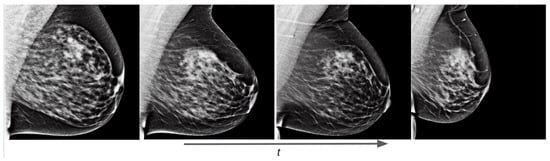

Training examples of the two separate conditional models using prompt text are shown in Figure 13 for the OMI-H dataset and Figure 14 for the VinDr dataset. We observe that the fine-tuning technique allows the generation of meaningful images from epoch one. For the Hologic example, we can observe that, as the training process increases, the mammogram reduces its shape in accordance to the area described in the prompt text. Moreover, it can be noticed that our models differentiate the overall intensity appearance of mammograms, which is different between Hologic and Siemens systems.

Figure 13.

Training evolution of SD with Hologic images at epochs 1, 3, 6, and 10. The prompt is: “a mammogram in MLO view with small area”.